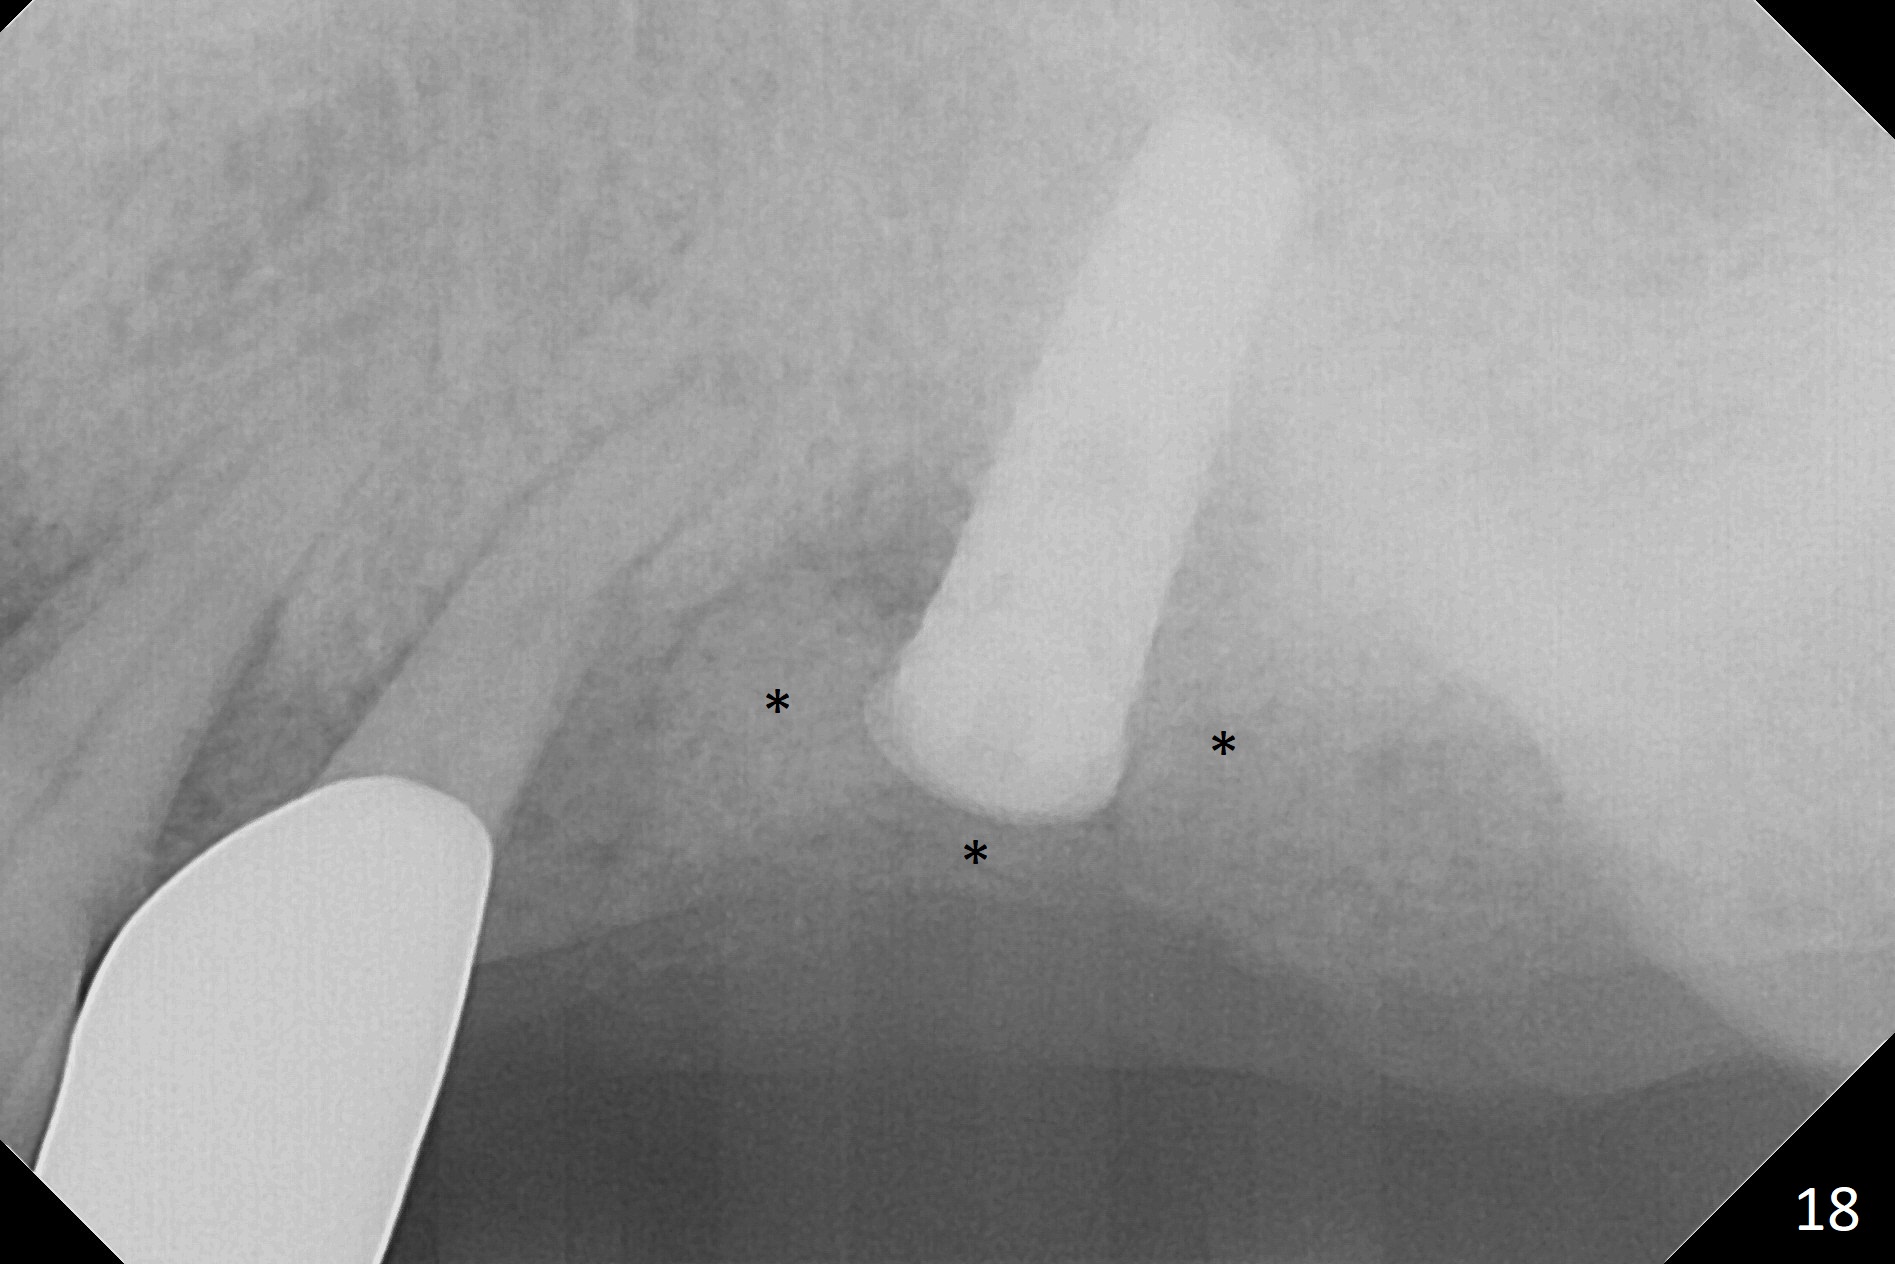

The amount of the bone graft mesial and distal the implant seems to reduce 3 and 4 months postop, respectively (Fig.6,7 arrowheads). When the acrylic is cut off 4 months postop, the bone graft is loose. The gingiva is unhealthy. The abutment and implant are loose. A healing abutment is placed (5x4 mm). The implant is torqued to 35 Ncm 6 months postop with the healing abutment reapplied. The patient will return for follow up nearly 9 months postop. A larger healing abutment will be used if the implant is stable. Two weeks later, use a smaller restorative abutment for easy impression. In fact the implant is unstable with #15 mesial shift due to abnormal occlusion with #17 (Fig.8). Bone density around the implant is low (* in Fig.9 (PA), 10,11 (CT sagittal, coronal sections)). A healing screw is placed for self healing. A 2nd option is to remove the implant (Fig.12), BEB (Fig.13) and place the implant deeper (Fig.14) or larger one (5.5-6.5x13 mm). The 3rd option is to place larger and longer implants (Fig.15 (tapered), 16 (cylindrical)). The implant access has partially closed 14 months postop, but there is a small buccal opening with sanguine exudate. Incision reveals severe bone loss around the implant; the mobile tooth #15 is extracted (Fig.17). After debridement and irrigation with normal saline, Vera Graft (Fig.18 *) and Collagen plug are placed with periodontal dressing.